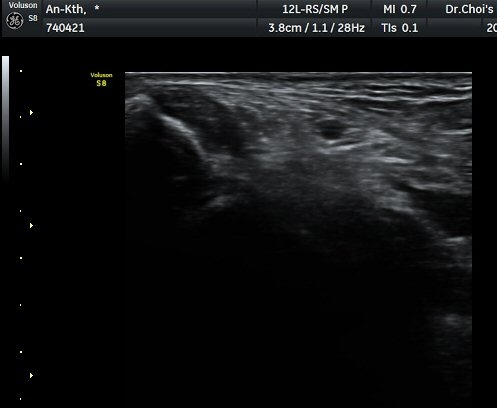

ÃÊÀ½ÆÄ ¼Ò°ß

¹ß¸ñ ³»Ãø Ⱦ´Ü¸é°Ë»ç¿¡¼­ ±ä¾öÁö±¼°î°Ç(FHL)ÀÇ ºÎÁ¾°ú °Ç ÁÖÀ§ ¼ö¾×Àú·ù°¡

°üÂûµÈ´Ù(±×¸² 1, 2, 3). ±ä¾öÀÚ±¼°î°Ç Á¾´Ü¸é°Ë»ç¿¡¼­ ±ä¾öÁö±¼°î°ÇÀÇ ºÎÁ¾°ú